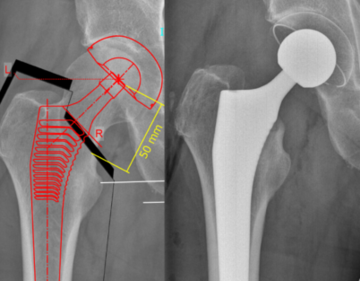

In der Hüftendoprothetik verwenden wir knochensparende zementfreie Kurschaftprothesen sowie zementfreie und zementierte Geradschaftprothesen. Die Gelenkpfannen, bestehend aus Titan mit einem Polyethyleninlay, werden in Regel zementfrei im Becken verankert. Nach Anfertigung spezieller Röntgenaufnahmen vor der Operation erfolgt eine genaue digitale Planung der Prothese, individuell auf die Anatomie des Patienten abgestimmt.

Digitale Planung einer Hüftprothese

(Optimys Kurzschaft)